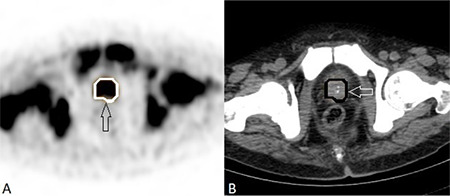

Objectives: To evaluate the relationships between volumetric 68Ga-prostate-specific membrane antigen (PSMA) positron emission tomography/computed tomography (PET/CT) parameters, Gleason score (GS), prostate-specific antigen (PSA) levels, histopathological data, and metastatic status in newly diagnosed prostate cancer (PCa) patients and to assess the predictive factors for progression despite treatment.

Methods: A total of 78 newly diagnosed patients with PCa who had 68Ga-PSMA PET/CT scans were included. Clinical parameters, histopathological data, and metastatic status were documented, and volumetric parameters of primary prostate lesions were measured. All obtained data were compared statistically.

Results: Primary prostate tumor maximum standardized uptake value (SUVmax) and GS were significantly related to serum PSA levels (p<0.05). PSA levels and SUVmax values were significantly higher in patients with lymph node metastases than in those without. GS was found to be significantly increased in metastatic patients. PSMA-derived tumor volume (PSMA-TV) and total lesion PSMA of the primary lesion had a significant relationship with PSA value, GS, and regional lymph node metastases. Receiver operating characteristic analysis, conducted in patients with metastatic and localized disease, identified the cutoff value for SUVmax as 10.85. According to the results of the logistic regression analysis, PSMA-TV was found to be a predictive factor for progression despite treatment.

Conclusion: 68Ga-PSMA PET/CT remains an invaluable imaging modality that should be considered first in PCa staging because of its superior compatibility with clinical and histopathologic data. The importance of this method goes beyond diagnostic accuracy; it also extends into the predictive domain, where the PSMA-TV value of primary prostate lesions is a potential predictor of treatment efficacy. This information is valuable for personalizing patient treatment, improving prognostic accuracy, and predicting clinical outcomes.